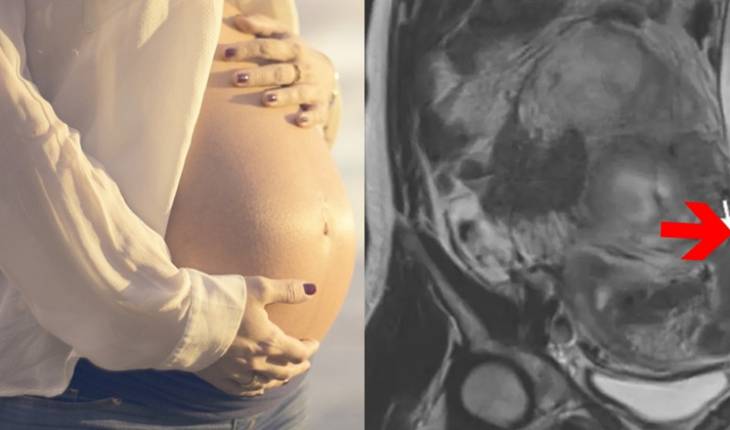

Bebê coloca as pernas para fora do útero da mãe e imagem mostra raridade

The New England Journal of Medicine divulgou um artigo sobre o caso raro.